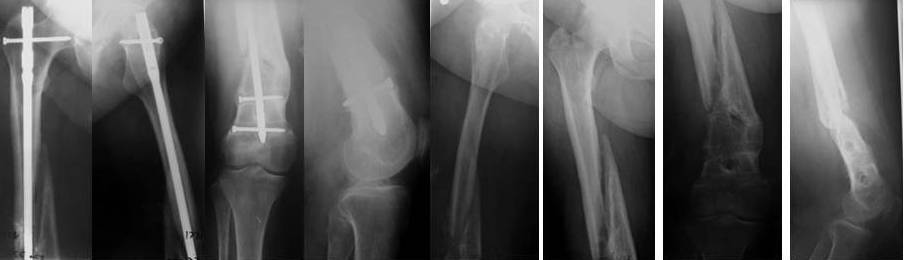

пациентка 58лет, ожирение III СТ., сахарный диабет 2 типа (субкомпенсированный), 3 года назад БИОС бедра в г.Н-ске по поводу перелома в н\3, нагрузка разрешена на ногу сразу, несмотря на вес, качество и метод остеосинтеза, а теперь красота писанная!! штифт убрали неделю назад с тех. трудностями, есть мнение выполнить, клиновидную остеостомию на уровне деформации, ретроградно с рассверливанием Expert с клинком и костной пластикой. Ваше мнение???